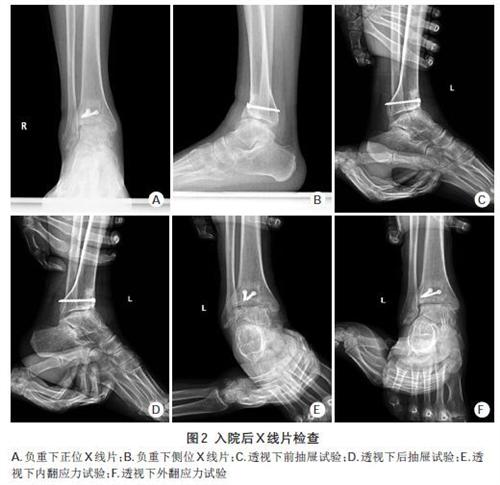

相关图片